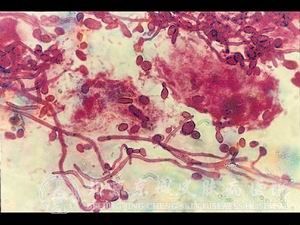

念珠菌病的类型有哪些?念珠菌病严重困扰着我们身边的很多人,很多患者关心这个念珠菌病的类型有哪些,但目前有很多患者对念珠菌病的类型有哪些不了解,错过了较佳念珠菌病治疗 时机,从而导致念珠菌病病情发展严重,增加了念珠菌病患者的痛苦,同时也增加了念珠菌病 的治疗难度。知道念珠菌病 的诊断方法,就可以及早的采取措施,预防念珠菌病的发生。

北京京城皮肤医院指出,念珠菌病的类型包括皮肤念珠菌病、粘膜念珠菌病、内脏念珠菌病三种。这些类型疾病感染的部位是不同的,所以才可以划分为三种类型。